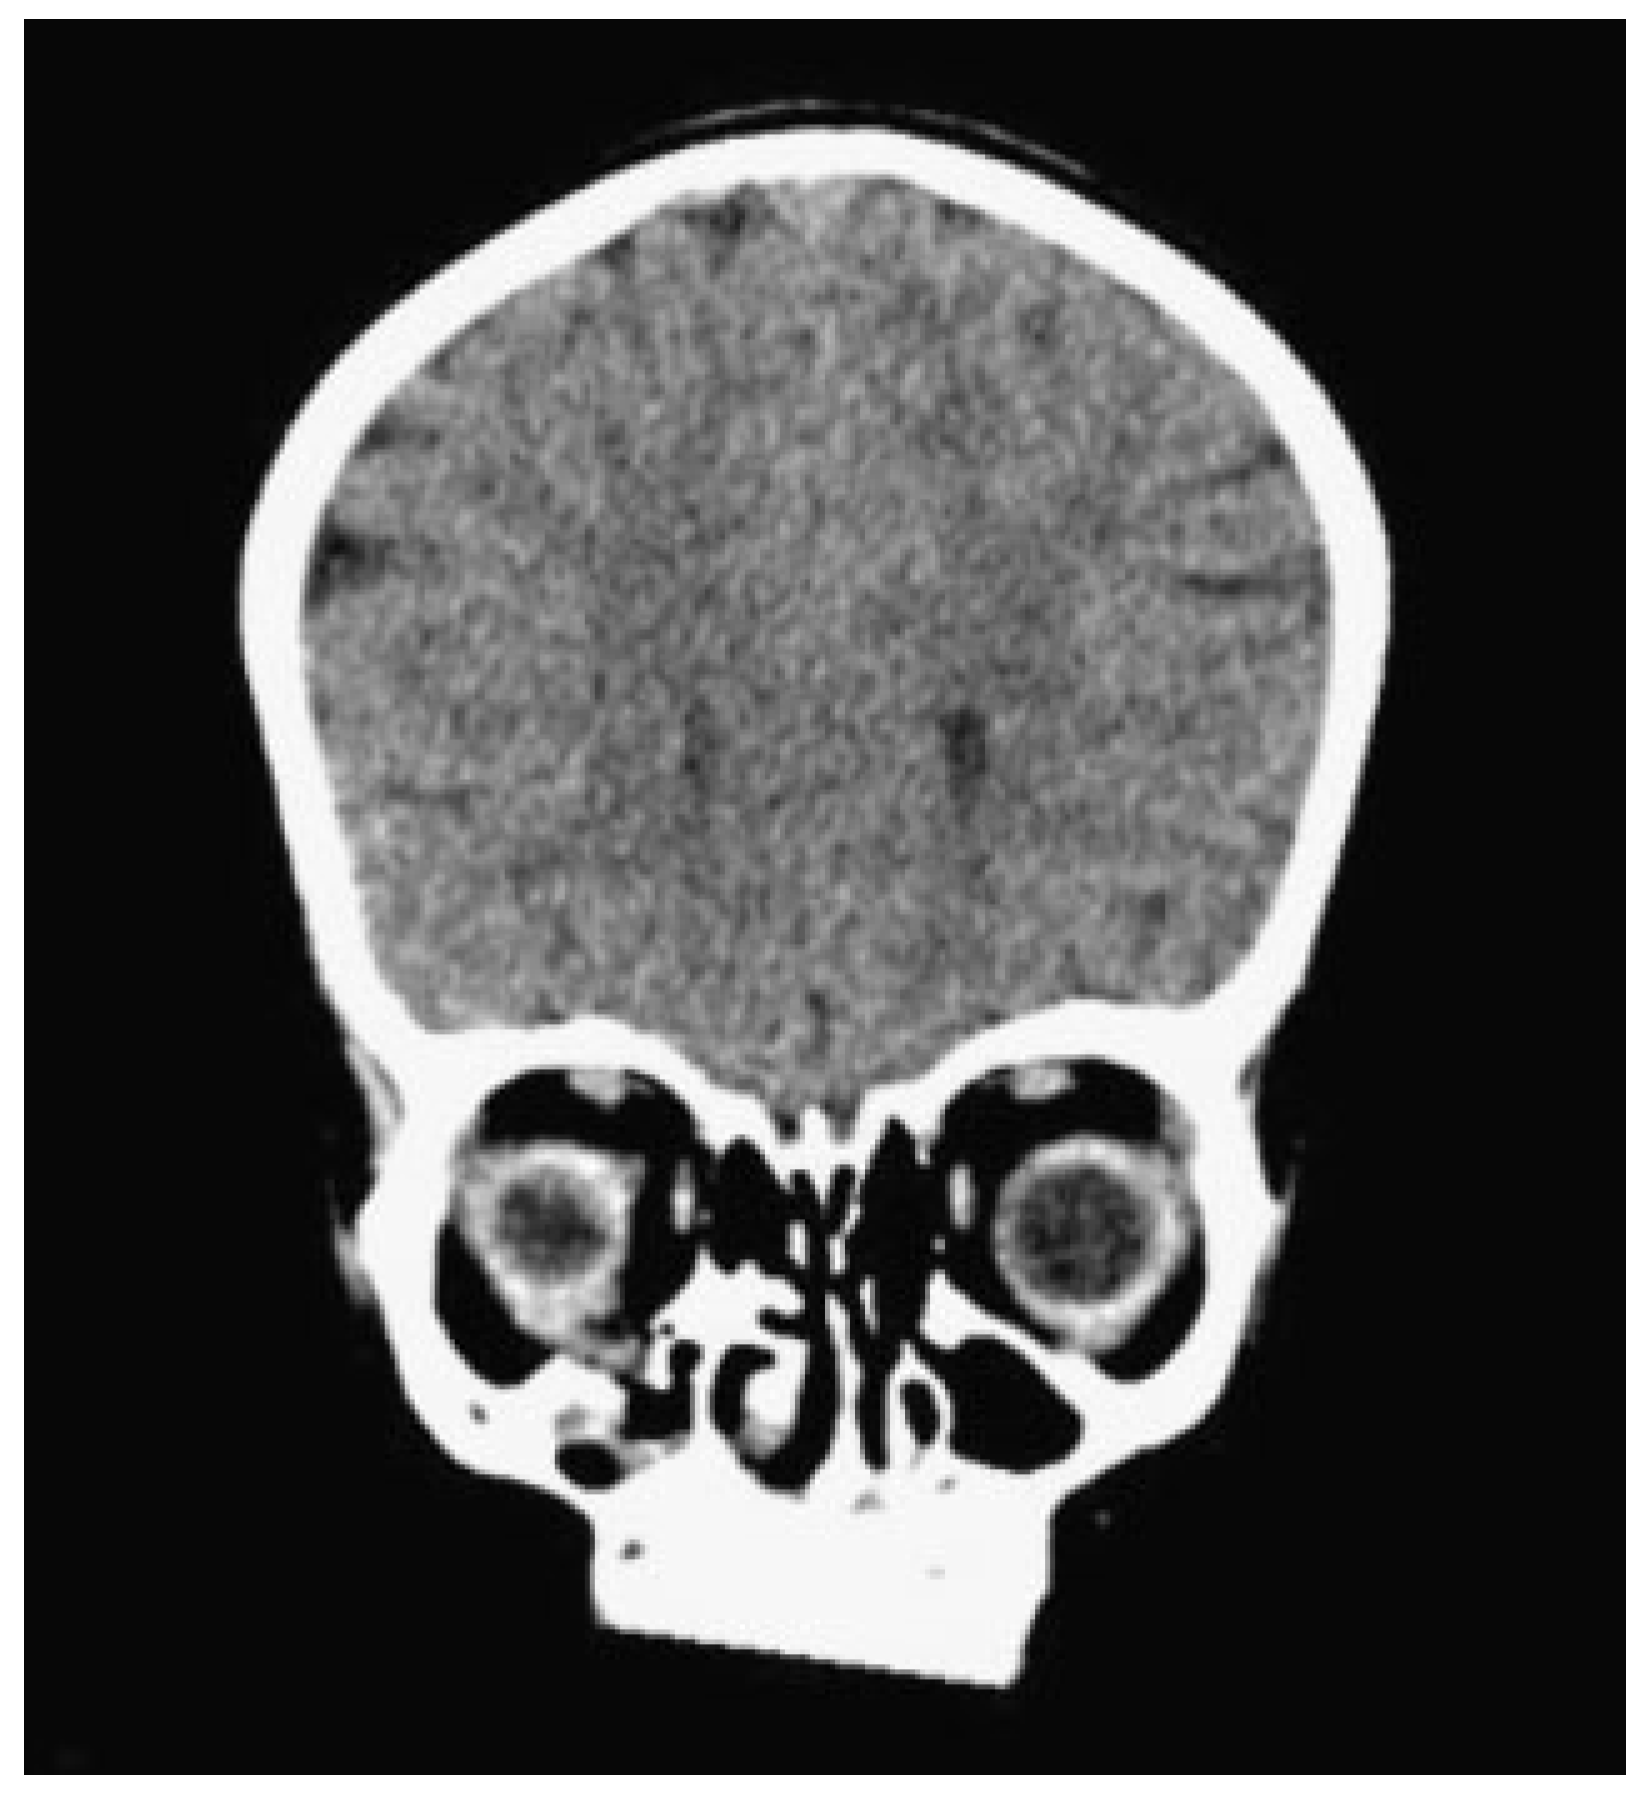

A 3-year and 10-month-old girl was referred from a regional hospital for a “second opinion” about an orbital fracture caused by a fall. An orbital computerized tomography (CT) scan made at the initial hospital showed a pure blowout fracture of the right orbital floor with dislocation of orbital contents (Figure 2). The size of the defect was 8.8 × 8.6 mm. There was no diplopia. The sensibility of the infraorbital nerve was undisturbed but possibly unreliable. The eye motility was normal. Hertel exophthalmometry values were: 10, 96, and 11. Due to periorbital edema and lack of clinical symptoms, the initial approach was conservative. Twenty days later an enophthalmos was noticed, without diplopia.

Figure 2. Coronal orbital computed tomography scan of our 3-year-old patient after blunt orbital trauma, depicting a right-sided orbital (floor) blowout fracture with herniating orbital contents. Note the small lumen of the maxillary sinus associated with very young age.